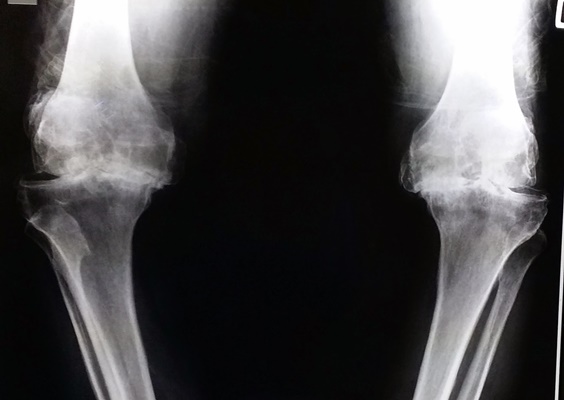

ในวันนี้ขอยกตัวอย่างผู้ป่วยโรคข้อเข่าเสื่อมทั้ง 2 ข้าง ที่ทำให้ผู้ป่วยมีอาการปวดข้อเข่า เดินลำบาก ข้อเข่าผิดรูป เดินเซและหกล้มได้ง่าย ซึ่งทำให้ผู้ป่วยใช้ชีวิตอย่างลำบากเป็นระยะเวลานานถึง 2 ปี ผู้ป่วยมีอาชีพรับราชการตำรวจ ทนทุกข์ทรมานจากอาการปวดเข่ามานาน ผู้ป่วยให้ประวัติว่า “เคยเจ็บเข่าจากอุบัติเหตุเล่นฟุตบอล จากนั้นก็เจ็บเข่าเป็นๆ หายๆ เรื่อยมา ในระยะสองปีมานี้อาการปวดเพิ่มขึ้นมากเรื่อยๆ คนรอบข้างเริ่มทัก โดยเฉพาะคุณแม่บอกว่าเดินไม่สวย เดินแปลกๆ เดินขาไม่ตรง เราก็ไม่ค่อยใส่ใจเท่าไหร่ จนมีอาการเจ็บมากจนทนไม่ไหว มาพบแพทย์ที่โรงพยาบาล แพทย์ได้ส่งตรวจทำการเอกซเรย์ เห็นได้ชัดเจนว่ากระดูกเข่าของเราชิดเข้าด้านในท่ายืนตรง แพทย์ได้แนะนำให้รักษาโดยการผ่าตัด ตอนแรกรู้สึกกังวล แต่เห็นกระดูกเข่าของตนเองจากภาพถ่ายรังสีแล้วก็คิดว่าถ้าปล่อยทิ้งไว้เข่าก็จะต้องชิดเข้ามากเรื่อยๆ ยังไงก็ต้องผ่าอยู่ดี และคิดว่าการเข้ารับการผ่าครั้งนี้ต้องเจ็บ ต้องปวดและใช้เวลาพักฟื้นนานแน่ๆ มีความกังวลว่ากระบวนการรักษาการผ่าตัดมันเป็นอย่างไร แพทย์จะทำอะไรกับเราบ้าง แต่หลังจากการได้คุยและได้รับคำแนะนำจากแพทย์ที่จะทำการผ่าตัด พร้อมกับเข้าไปศึกษาถึงวิธีการรักษา การปฏิบัติตัวและตัวอย่างประวัติการรักษาจากผู้ป่วยที่เคยรับการผ่าตัดรักษาเปลี่ยนข้อเข่าเทียมแล้ว ได้คลายความกังวลลงมาบ้าง หลังจากรับการรักษาด้วยการผ่าตัดเปลี่ยนข้อเข่าเทียมแล้วไม่ได้เจ็บปวดอย่างที่คิดไว้ สองวันแรกหลังผ่าตัดไม่ปวดเลย และเริ่มไปทำกายภาพ หัดเดินด้วยไม้สี่ขา หัดเหยียดเข่า งอเข่า ประมาณวันที่สี่เริ่มมีอาการระบม ปวด แพทย์ได้ให้ยาแก้ปวด อาการปวดทุเลาลงไป ทำกายภาพต่อได้สบาย มาตอนนี้หลังผ่าตัดประมาณยี่สิบวัน รู้สึกดีมาก แผลแห้งดี งอเหยียดเข่าได้เต็มที่ ยืนขาตรง เดินตรง เหมือนกับได้ชีวิตใหม่ขึ้นมาอีกครั้ง” สำหรับผู้ป่วยรายนี้ เนื่องจากเข่าของผู้ป่วยมีอาการผิดรูปทั้ง 2 ข้าง ทำให้ไม่สามารถเดินได้เป็นปกติ หลังจากที่ได้พูดคุยและอธิบายถึงข้อดีและความเสี่ยงจากการผ่าตัด เช่น โอกาสของการติดเชื้อ การเกิดลิ่มเลือดอุดกั้นในเส้นเลือดดำ การควบคุมอาการปวดหลังการผ่าตัด ก็ได้พิจารณารักษาด้วยการผ่าตัดเปลี่ยนข้อเข่าเทียมพร้อมกันทั้ง 2 ข้างให้กับผู้ป่วย หลังการผ่าตัดได้มีการให้ยาระงับปวดด้วยการวางสายเพื่อให้ยาลดอาการปวดที่โพรงประสาทในส่วนกระดูกสันหลัง ซึ่งผลการผ่าตัดทุกอย่างเป็นไปตามเป้าหมายที่วางไว้ คือ ลดอาการปวดข้อเข่าให้กับผู้ป่วย แก้ไขความผิดรูปของข้อเข่าทั้ง 2 ข้าง ทำให้ผู้ป่วยสามารถกลับมาเดินได้อย่างปกติ ทำให้ผู้ป่วยสามารถกลับไปใช้ชีวิตในสังคมได้อย่างมีความสุข ทำให้คุณภาพชีวิตของผู้ป่วยดีขึ้นเป็นอย่างมาก